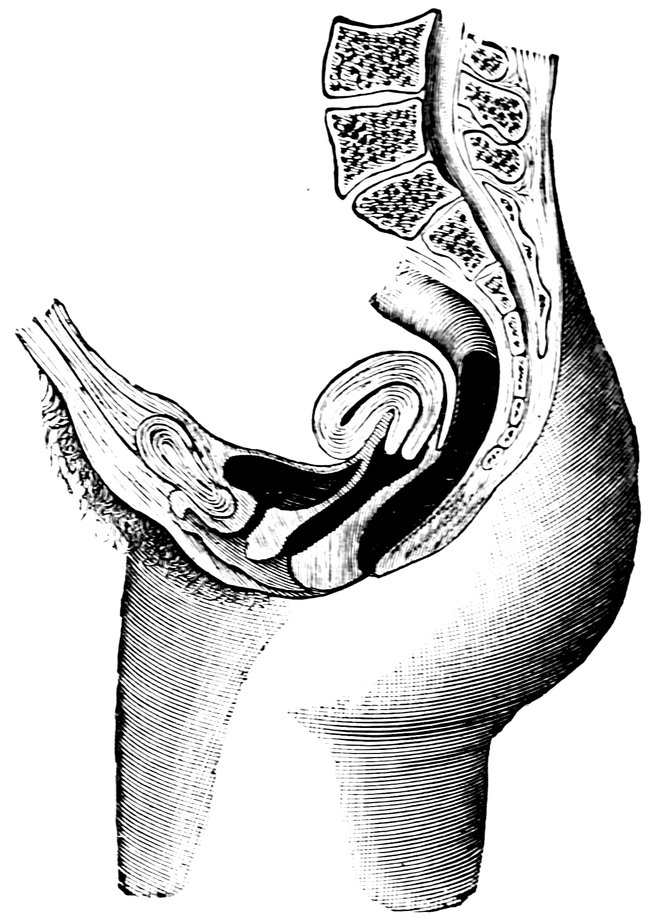

| 2. | Portion of the pelvic viscera in the female, etc. | 9 |

| 14. | Sagittal section of the female pelvis | 56 |

| 80. | Anteflexio Uteri (after A. Martin) | 518 |

Fig. 2.—Portion of the pelvic viscera in the female, and their relation to the muscles of the pelvic outlet (or perineal muscles), shown in the left half of the pelvis, seen from the right side.—The parametrium. (From Toldt: Atlas of Human Anatomy.—Rebman Company, New York.)